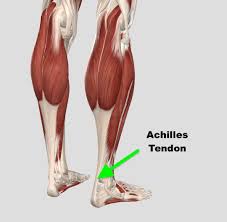

کوتاهی تاندون آشیل

کوتاهی تاندون آشیل ( به وضعیتی گفته میشود که تاندون آشیل – که عضلههای ساق پا را به استخوان پاشنه متصل میکند – کوتاهتر از حالت طبیعی است. این کوتاهی میتواند باعث محدود شدن حرکت مچ پا شود، بهخصوص در حرکت خم شدن به سمت بالا (dorsiflexion)، و منجر به مشکلاتی مانند: راه رفتن روی […]